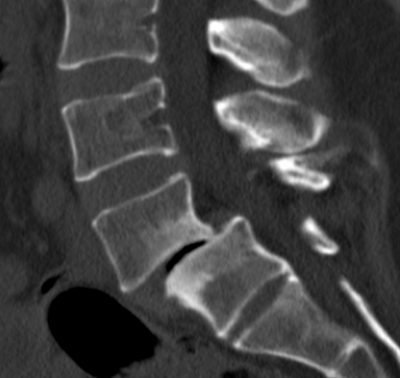

Ο απεικονιστικός έλεγχος ανέδειξε σπονδυλολίσθηση 2ου βαθμού σε έδαφος σπονδυλόλυσης (λύση της συνέχειας του οστού στον ισθμό, δηλαδή μεταξύ των δύο αρθρώσεων).

Διενεργήθη διαδερμική (ελάχιστα επεμβατική) σπονδυλοδεσία στο επίπεδο Ο4/Ο5